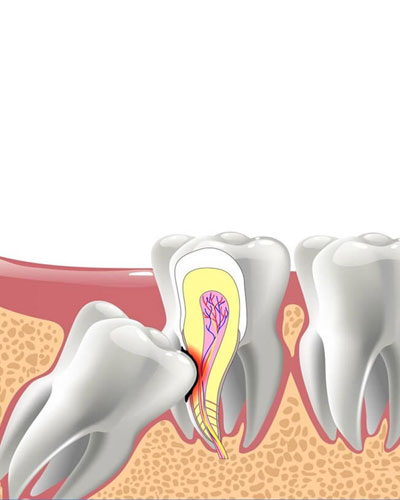

răng số 7 bị tấn công – lung lay, viêm tủy

Răng khôn không có chức năng ăn nhai, nhưng lại gây ra hàng loạt rắc rối nghiêm trọng nếu để lâu:

Làm tiêu xương hàm, viêm tủy, mất răng kế bên